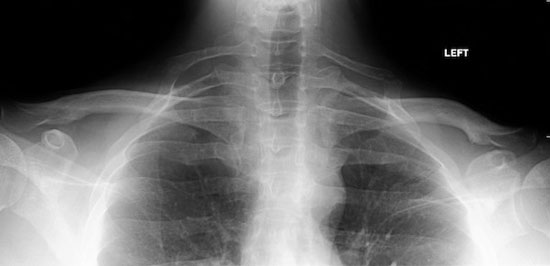

۳- برخی افراد یک دنده اضافه دارند

اغلب افراد بالغ ۲۴ دنده (۱۲ جفت) دارند، اما از هر ۵۰۰ نفر یک نفرشان دنده اضافهای به اسم دنده گردنی دارد. این استخوان که از پایه گردن و درست از بالای ترقوه رشد میکند کاملا هم شکل نگرفته و گاهی اوقات صرفا نوار نازکی از فیبرهای بافتی است.

این دنده اضافه جدا از شکلی که دارد چنانچه در مجاورت رگهای خونی و عصبها آسیب ببیند میتواند مسائل مهمی را متوجه سلامت انسان کند. در این موارد مشکلی تحت عنوان سندروم خروجی سینه رخ میدهد که از جمله علائم آن نیز درد موجود در شانه و گردن، بی حس شدن ناحیه دنده ها، انسداد رگهای خونی و دیگر مشکلات است.